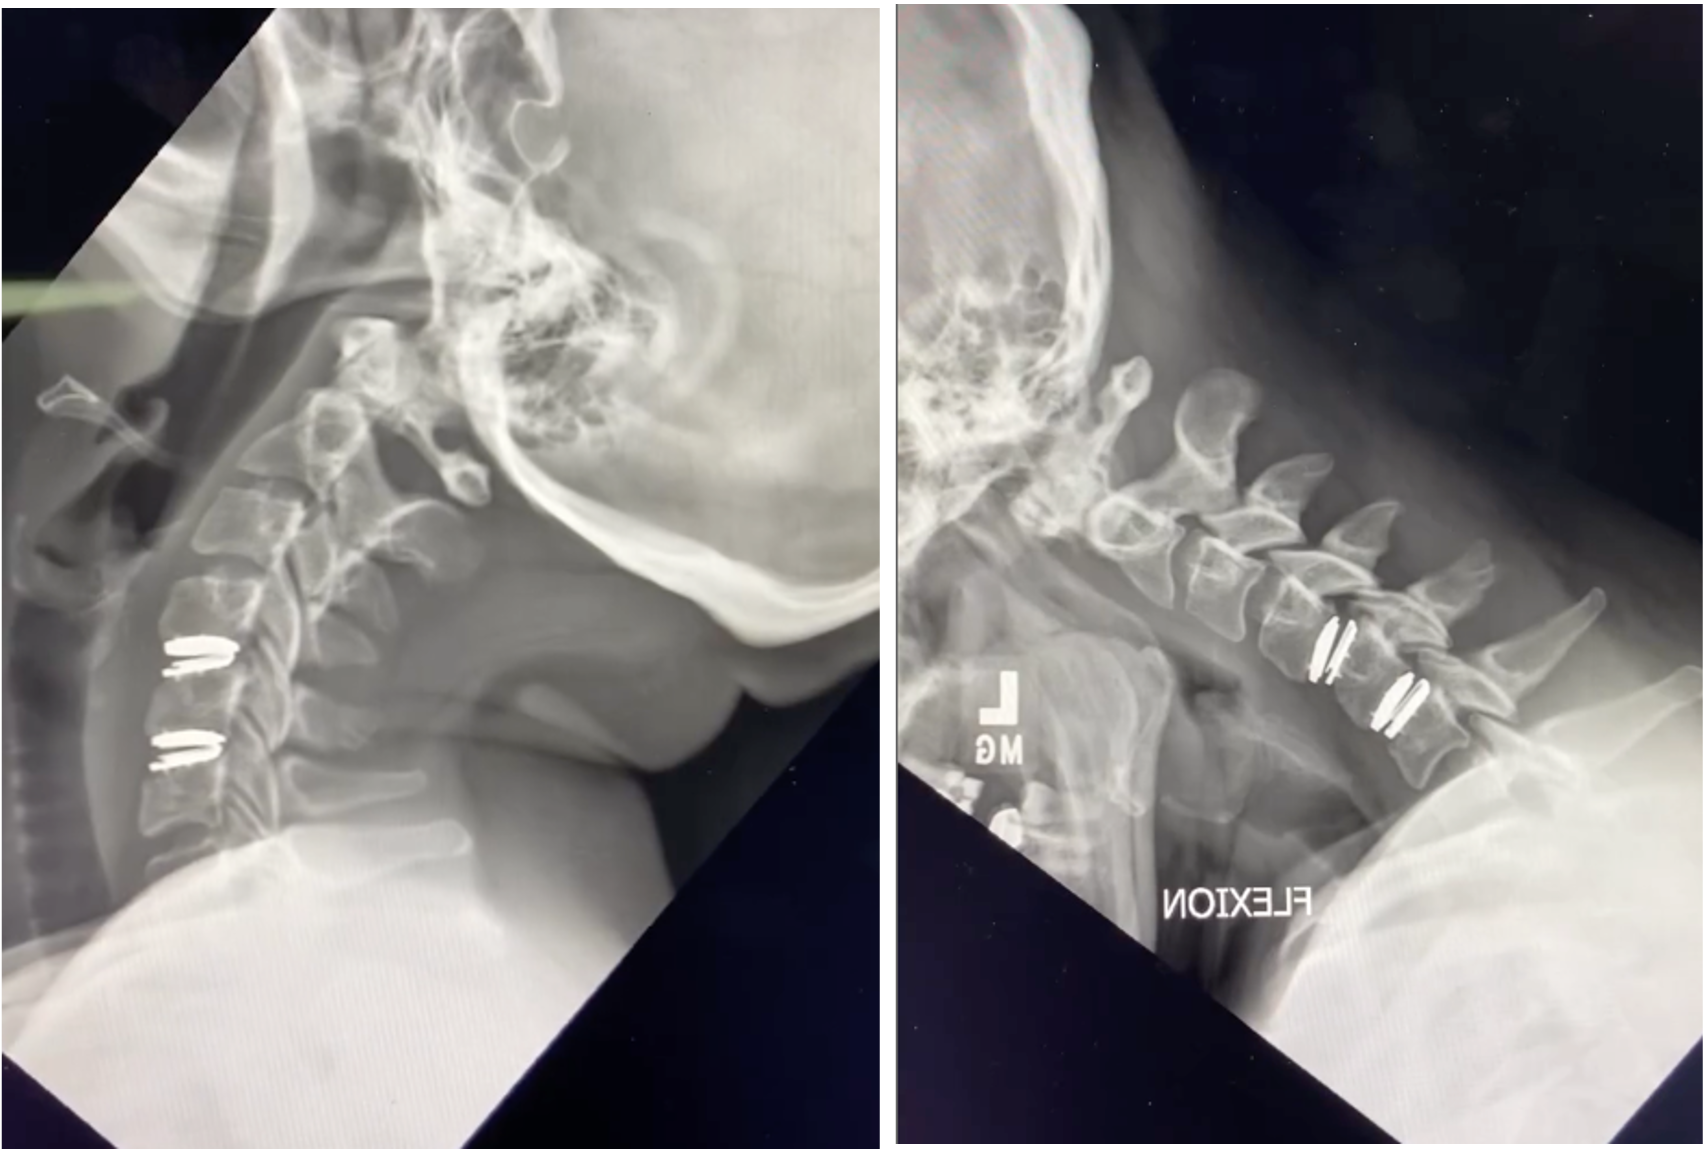

This is why a thorough evaluation — including a review of your MRI, dynamic X-rays (including flexion/extension XR), and full clinical picture — is essential before deciding between these two procedures. A surgeon who recommends one approach without carefully considering the other may not be offering you the full picture.

Cervical hybrid surgery — a fusion at one level, disc replacement at another This is where personalized decision-making becomes most important. A hybrid procedure combines ACDF at one level with disc replacement at an adjacent level. The goal is to address each level with the approach that's most appropriate for its specific condition — preserving motion where the anatomy supports it, and fusing where stability or bone quality demands it.

For example: if a patient has a herniated disc at C5-6 that is a good candidate for disc replacement, but significant arthritis and bone spurs at C6-7 that make fusion more appropriate, a hybrid procedure treats both levels optimally rather than applying a one-size approach to the whole spine.

Hybrid surgery requires a surgeon experienced in both techniques. The right multi-level strategy depends on your specific anatomy, the nature of the compression at each level, your age and activity demands, and your bone quality. It's one of the more individualized decisions in elective spine surgery, and it's exactly the kind of conversation I have with every multi-level patient before recommending a plan.

You'll need a thorough evaluation including an MRI of your cervical spine and dynamic XR of your cervical spine (pictures of your neck in different positions). Bring any existing imaging to your consultation — I review every scan personally and will walk you through exactly what I see and why I'm recommending a particular approach.